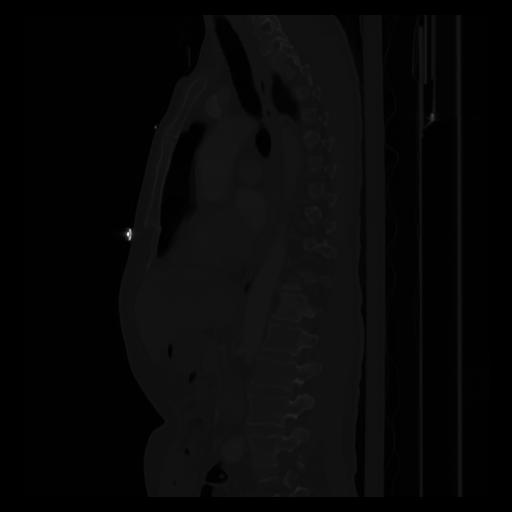

30 CUERPO,CE,Sagittal,3.000,CUERPO,Sagittal,